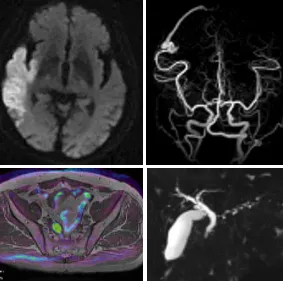

MRI(GE社製 SIGNA Pioneer 3T)

新しい3TのMRI装置で様々な部位の撮像が可能です。

当院では頭の検査が最短8分で撮影することが可能です。

更にDWIBSという検査を行っており全身の腫瘍をいち早く見つけることが可能です。